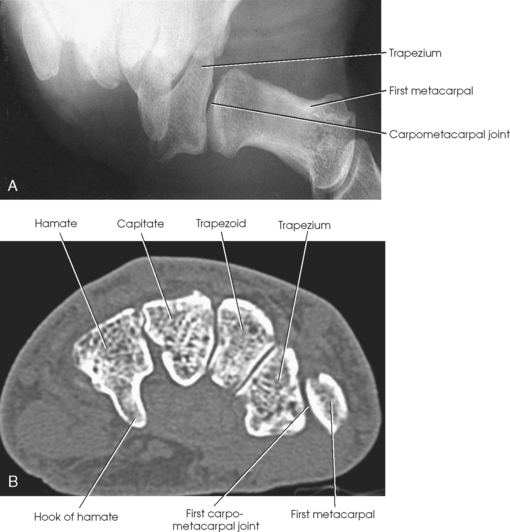

The carpals articulate with each other, the metacarpals, and the radius of the forearm. In the carpometacarpal (CMC) articulations, the first metacarpal and trapezium form a synovial saddle joint, which permits the thumb to oppose the fingers (touch the fingertips). The articulations between the second, third, fourth, and fifth metacarpals and the trapezoid, capitate, and hamate form synovial gliding joints. The intercarpal articulations are also synovial gliding joints. The articulations between the lunate and scaphoid form a gliding joint. The radiocarpal articulation is a synovial ellipsoidal type. This joint is formed by the articulation of the scaphoid, lunate, and triquetrum, with the radius and the articular disk just distal to the ulna (Fig. 4-9, C).

Beginning at the distal row of carpals on the lateral side, the trapezium has a tubercle and groove on the anterior surface. The tubercles of the trapezium and scaphoid constitute the lateral margin of the carpal groove. The trapezoid has a smaller surface anteriorly than posteriorly. The capitate articulates with the base of the third metacarpal and is the largest and most centrally located carpal. The wedge-shaped hamate exhibits the prominent hook of hamate, which is located on the anterior surface. The hamate and the pisiform form the medial margin of the carpal groove.

The anterior or palmar surface of the wrist is concave from side to side and forms the carpal sulcus (Figs. 4-2 and 4-3). The flexor retinaculum, a strong fibrous band, attaches medially to the pisiform and hook of hamate and laterally to the tubercles of the scaphoid and trapezium. The carpal tunnel is the passageway created between the carpal sulcus and flexor retinaculum. The median nerve and the flexor tendons pass through the carpal canal. Carpal tunnel syndrome results from compression of the median nerve inside the carpal tunnel.